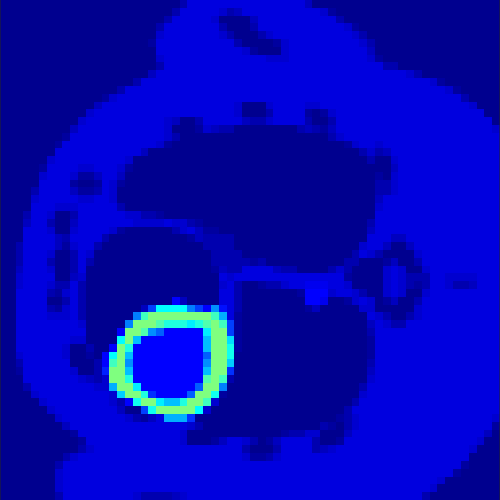

5.2 Monte Carlo Simulation

In order to test the behaviour of the proposed method in a more realistic, random-based test case, we performed a Monte Carlo simulation for dynamic SPECT imaging. First, we created a simple image phantom consisting of an outer and two inner circles which represents the structure of the region of interest (see figure 8(a)). Within those regions we assumed concentration curves over a time period of 90 time steps as displayed in figure 8(b). Based on the tracer intensity in an image frame at each time step, we created a variable number of random decay events (where the number is proportional to the average concentration in one pixel in the whole image frame per time step) with a probability proportional to the concentration in every subregion. They are detected by a virtual double head gamma camera rotating around the patient by 46 degrees per time step, which consists of 374 detector bins. Every simulated decay event is projected onto the scanner and counted by the corresponding detector bin.

Based on the sinogram data we applied the proposed algorithm in order to reconstruct the original image sequence. The results for both test cases are shown in figure 10.

As one can see, the method is able to reconstruct the regions properly, even in case of a low count number. Within a number of iterations (average of 100 outer and 10000 inner iterations), the algorithm presents a reasonable reconstruction of the region of interest and the corresponding regional tracer concentration curves. Here, the parameters were not optimized as in the case of the synthesized data sets in the previous section, but kept fixed as , and . With futher optimized parameter values one could possibly provide even better results.